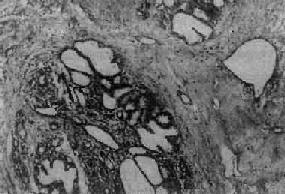

图13-24 纤维腺病

末梢导管、腺泡和间质均呈明显增生,部分腺泡及导管扩张,间质内有一些淋巴细胞浸润